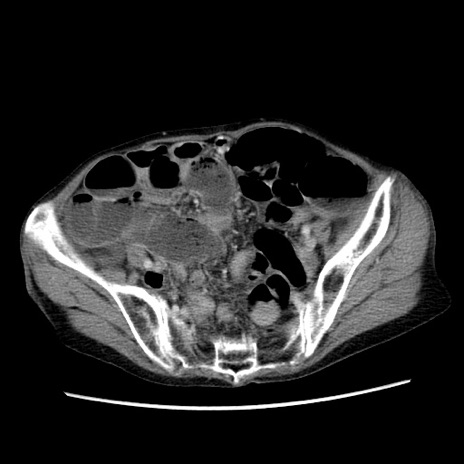

症例25(横断像)

【症例】80歳代女性

【主訴】胸のつかえ感

【現病歴】約9時間前に食後から胸のつかえた感じあり、嘔吐あり、来院。

【既往歴】胃癌(全摘)、胆摘、虫垂炎

【身体所見】心窩部に圧痛あり、反跳痛なし。

【データ】WBC 5700、CRP 0.05